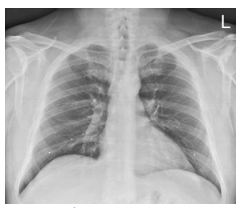

What projection is this?

AP